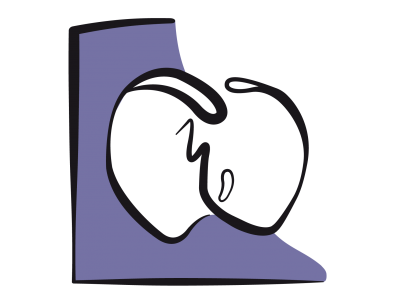

La boucle pression/volume (P/V) est une représentation graphique du travail ventriculaire au cours d'un cycle cardiaque. Elle a l'allure d'un quadrilatère posé sur la courbe de compliance et tournant en sens inverse des aiguilles d'une montre à partir du point télédiatolique (1); la contraction isovolumétrique conduit au point où commence l'éjection (2) et celle-ci se poursuit jusqu'au point télésystolique (3); la relaxation isovolumétrique amène au début du remplissage (4) et la boucle se termine au point télédiastolique (1) en suivant la courbe de compliance diastolique. Lorsqu'on varie le volume de remplissage d'un ventricule, tous ses points télésystoliques se trouvent alignés sur une quasi-droite appelée élastance maximale (Emax) dont la pente représente la contractilité du VG (Figure 23.6).

Figure 23.6: Boucle pression/volume lors d’insuffisance ventriculaire gauche (Ins VG , traits rouges) par rapport à une boucle normale (en jaune). La pente de la droite Emax (élastance maximale, qui reflète la contractilité, en bleu) et abaissée (en rouge) et la compliance ventriculaire (courbe verte) prend une allure restrictive (en rouge). Le volume éjecté (VS : volume systolique) diminue et le travail externe fourni (LVSW, left ventricular stroke work, représenté par la surface de la boucle) est plus faible. L’angle entre la pente Emax et la pente de la compliance est plus fermé. 1 : point télédiastolique; 1 →2 : contraction isovolumétrique; 2 : début de l’éjection; 2 → 3 : phase de l’éjection systolique; 3 : point télésystolique; 3 → 4 : relaxation isovolumétrique; 4 : début du remplissage; 4 → 1 : remplissage diastolique. VS: volume systolique (= Vtd – Vts). Le triangle compris entre la courbe de compliance, la droite Emax et la phase de relaxation isovolumétrique représente le travail de pression du VG.

La boucle P/V de l’insuffisance ventriculaire est caractérisée par un abaissement de l'élastance maximale (Emax), qui représente la force de contraction, et par une élévation de la courbe de compliance, qui représente la résistance au remplissage. Ces phénomènes conduisent à une diminution du volume systolique. Le rétrécissement de la surface de la boucle P/V traduit la baisse du travail éjectionnel fourni (stroke work). L’angle entre la pente Emax et la courbe de compliance étant étroit, une augmentation de la précharge par du remplissage déplace la boucle vers le haut et vers la droite, donc vers de plus grandes pressions et de plus grands volumes, mais n’améliore que faiblement le volume éjecté. Seul un effet inotrope positif augmente significativement le VS, parce qu’il redresse la pente de Emax (ouverture de l’angle entre la pente Emax et la courbe de compliance).